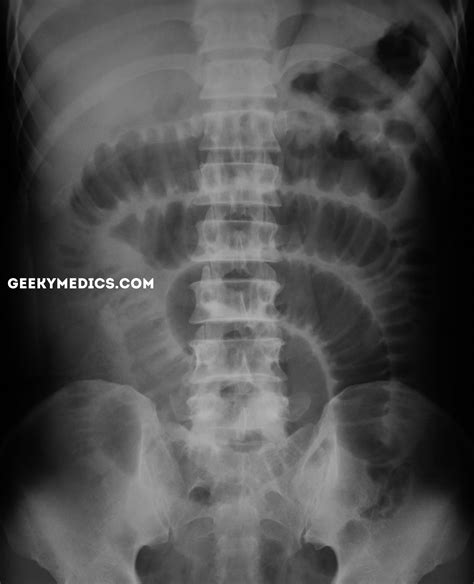

Common Findings in a Normal Abdominal X Ray

A Normal Abdominal X Ray typically reveals the following structures and patterns:

• Gas patterns in the stomach and intestines

• Clear outlines of the liver, spleen, and kidneys

• No signs of obstruction or perforation

• No evidence of foreign bodies

These findings indicate that the abdominal organs are functioning normally and there are no immediate concerns.